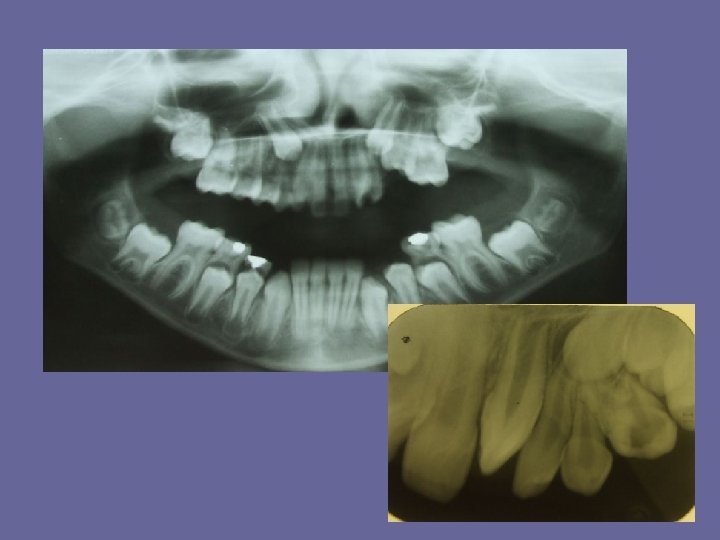

THE MIXED DENTITION • At the age of 6 years permanent teeth, usually the first molars or lower central incisors start to erupt. • As in the case of the deciduous teeth, eruption times are very variable and a range of 18 months on either side is not unusual. • There also some sex differences in the age of eruption. Girls are 1/2 year ahead of boys. • During this century there has been a tendency towards earlier eruption of permanent teeth in the developed countries ( "secular trend" ). It has mainly been due to the earlier onset of puberty, and indirectly to better child health and nutrition

THE MIXED DENTITION Typical ages of eruption: • first molar. . . 6 -7 years • central incisor. . . 6 -7 years • lateral incisor. . . 7 -8 years • canine. . . 9 -13 years • premolars. . . 9 -13 years • second molar. . . 11 -14 years • third molar. . . 17 -30 years The permanent teeth erupt first in mandible and then in maxilla except the premolars which erupt first in maxilla.

THE MIXED DENTITION • At the time of eruption 2/3 of the root is generally formed. Thereafter, 1, 5 -3 years are needed to complete root length and even longer to close the root apices to the mature size.

REPLACEMENT OF THE TEETH The eruption can be divided into periods: 1. The first period means a replacement of incisors, after which a break (usually 2 years) follows. 2. At the age of 10 -12 years the second period is performed. So the canines and premolars erupt.